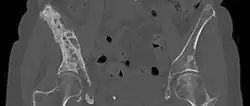

| 3D rendered CT scan of bone metastases of the hip bone, in a 60 year old woman with parotid gland cancer. Large lesions are seen on the ilium on the more distant side. Involvement of the vertebral column has caused a compression fracture. | |